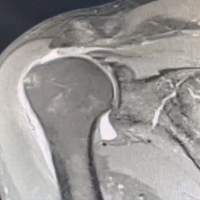

Figure 2: Magnetic resonance imaging of the right foot showing large irregular multiloculated expansile cystic lesion measuring approximately 4.1 × 3.1 × 2.2 cm, involving the talar dome and neck reaching up to the anterior articular surface. The lesion appears as heterogeneously hyperintense on T2/short tau inversion recovery images and iso to hypointense on T1-weighted image with multiple intrinsic thick enhancing septae causing loculation with multiple intrinsic blood-fluid level.

X-Rays of the foot of the patient showed a lytic lesion of the right talus bone. A contrast-enhanced MRI was also advised, which showed a large irregular multiloculated expansile cystic lesion, measuring approximately 4.1 × 3.1 × 2.2 cm, involving the talar dome and neck reaching up to the anterior articular surface. The lesion appeared as heterogeneously hyperintense on T2/Short tau inversion recovery images and iso to hypointense on T1-weighted images with multiple intrinsic thick enhancing septae causing loculation with multiple intrinsic blood-fluid levels, suggestive of ABC, and histopathological and clinical correlation was advised. Upon follow-up, image-guided fine needle aspiration cytology (FNAC) and biopsy of the patient were done. The FNAC was suggestive of few scattered multinucleated giant cells along with few degenerated cells against hemorrhagic background, likely a benign lesion (Fig. 3). The biopsy result reported fragmented bone tissue with hemorrhagic cystic spaces lined by osteoclastic giant cells and mononuclear cells with mild anisonucleosis with two possible differentials: Giant cell tumor and ABC, both being quite rare in the talus.